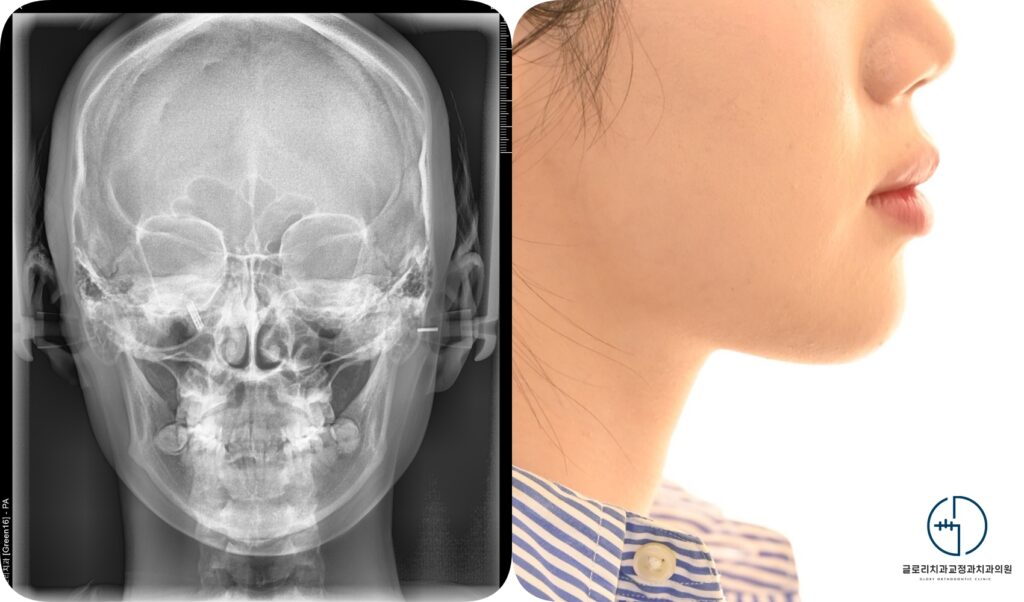

상봉동 교정치과 에서는 엑스레이를 이용한 정밀 진단이 필요하다 설명드립니다.

측모사진과 여러 다각도 분석을 통해 해당 케이스는 골격성 1급 부정교합임을 파악합니다.

이는 상하악의 전후방관계는 비교적 안정적인 상태를 의미하며 턱뼈 위치 자체에는

큰 불균형이 없음을 뜻합니다. 따라서 이번 총생의 주된 원인은 골격적 문제라기보다는

치열 내 공간 부족에 의해 발생한 배열 이상으로 판단할 수 있습니다.